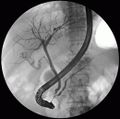

قناة الپنكرياس pancreatic duct أو قناة ڤيرسونگ duct of Wirsung (تُعرف أيضاً بقناة الپنكرياس الرئيسية لوجود قناة پنكرياس ملحقة)، هي قناة تصل الپنكرياس بالقناة الصفراوية المشتركة لتوصيل عصارة الپنكرياس التي تساعد في عملية الهضم. تندمج قناة الپنكرياس مع القناة الصفراوية المشتركة قبل أمپولة ڤاتر، اللذان يخترقان بعدها الطرف الأوسط من الجزء الثاني من الاثنا عشر.[1]

إنضغاط، انسداد، أو التهاب قناة الپنكرياس قد يؤدي إلى الإصابة بالتهاب الپنكرياس الحاد. السبب الأكثر شيوعا لانسداد القناة هو تجمع حصى في القناة الصفراوية، أو ظهور حصى مرارية في القناة الصفراوية المشتركة. يمكن للإنساد أن يكون بسبب التهاب في الاثنا عشر. يمكن أن تؤدي الحصاة الصفراوية لانسداد في نهاية أمپولة ڤاتر، حيث يُسد عندها مجرى العصارة الصفراوية والعصارة الپنكرياسية المتجهتان إلى الاثنا عشر. انسداد وتوقف العصارة الصفراوية (المرارية) يمكن أن يؤدي لالتهاب الپنكرياس.[7]